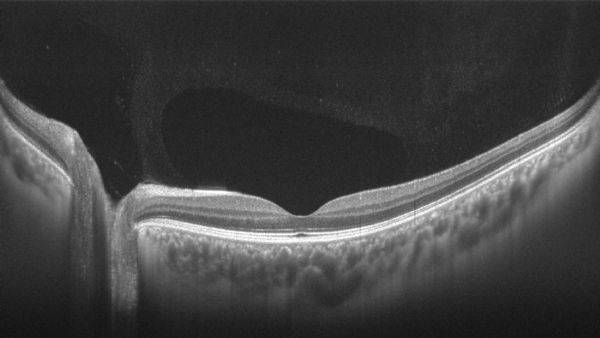

16mm视盘-黄斑区断层成像(团队供图)

黄斑区OCTA成像效果(团队供图)